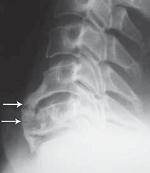

![]() На рентгенограмме № 4 изображен межпозвонковый сегмент в далеко зашедшей стадии дегенерации. Спондилёз второй степени в сочетании со снижением межпозвонкового промежутка говорит о том, что в прошлом на данном уровне имелась протрузия межпозвонкового диска, которая была стабилизирована развившейся стадией фибротизации поражённого диска (что хорошо видно на МРТ № 37). Бывает, что спондилёз может травмировать эпидуральную клетчатку (при движении позвоночника), в результате чего в ней возникают асептические воспалительные процессы. Эпидуральная клетчатка со временем уплотняется, склерозируется, в ней появляются фиброзные тяжи, которые могут деформировать спинномозговой корешок, вызвать его натяжение или сдавление. А при значительном увеличении (разрастании) спондилёза может развиться стеноз спинномозгового канала второго типа (первый тип стеноза — врождённый, второй — приобретённый), что довольно часто бывает при срыве адаптивных механизмов во время развития дегенеративно-дистрофических процессов в межпозвонковых дисках. Рентгенограмма № 5 ![]() МРТ № 38 ![]() На рентгенограмме № 5 шейного отдела позвоночника — выраженный спондилёз третьей степени и остеофитоз, что хорошо видно на МРТ № 38 сегментов шейного отдела позвоночника. В целом можно сказать, несмотря на то что спондилёз и остеофиты являются следствием определённых заболеваний позвоночника и в некоторой степени способствуют биомеханическим нарушениям в других сегментах позвоночника, всё же они небесполезны. Во многих случаях это своеобразная «скорая помощь» организма в ответ на невозможность осуществить полноценную регенерацию повреждённого позвоночно-двигательного сегмента. Данные костные наросты хоть и ограничивают движение сегмента, но тем самым предупреждают и замедляют его дальнейшее разрушение. Так что если при обследовании позвоночника у вас обнаружат спондилёз или остеофиты, то не стоит бояться этого диагноза. На самом деле всё не так страшно, как кажется на первый взгляд. Рентгенограмма № 6 ![]() МРТ № 39